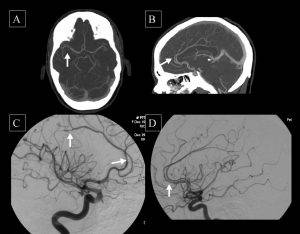

⚫ سی تی آنژیو گرافی: در این روش ماده حاجب از طریق ورید بیمار وارد جریان خون شده و دستگاه می تواند به وسیله یک نرم افزار رایانه اي، تصاویر سه بعدی دیجیتال را از عروق کرونری ثبت کند.

⚫ آنژیو گرافی: در این روش ماده حاجب به مسیر شریانی دست ها یا پاها تزریق می شود و تصاویر عروق به صورت فیلمبرداری دیجیتال و از زوایای مختلف به دست میآید.

اما آنژیوگرافی عروق کرونری به مراتب دقیق تر از دستگاه های سی تی آنژیوگرافی عمل می کند. در آنژیو گرافی عروق کرونری ماده حاجب به رگ تزریق شده و از رگ فیلمبرداری می شود؛ به همین دلیل تکان های رگ مانعی برای ثبت دقیق تصاویر نخواهند بود.

اگرچه در تشخیص اولیه بیماری عروق کرونری میزان دقت سی تی آنژیو گرافی و آنژیوگرافی عروق کرونری تقریبا به یک میزان قابل قبول است اما زمانی که نیاز به تشخیص دقیق محل تنگی عروق، طول تنگی و درصد آسیب عروق باشد، سی تی آنژیوگرافی هرگز دقت آنژیوگرافی عروق کرونری را ندارد و دقت این دو با هم قابل مقایسه نیست و فقط آنژیو گرافی عروق کرونری قادر به تشخیص این نکات ظریف است.